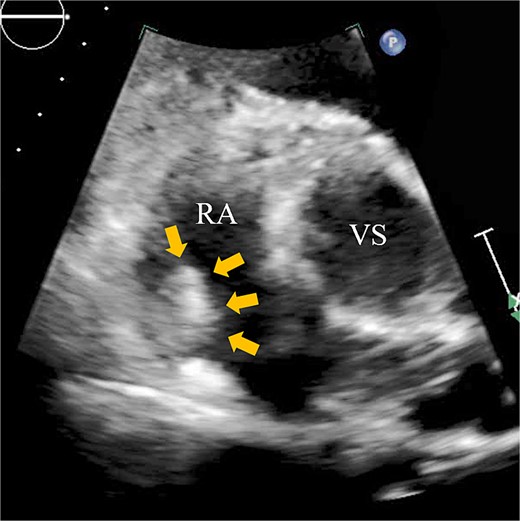

A 74-year-old male with a history of chronic atrial fibrillation (AF) for over 10 years, cardioembolic stroke, and cerebral hemorrhage, who had undergone LAA closure using the WATCHMAN device 1 year prior, was admitted after a follow-up contrast-enhanced CT scan revealed a 25-mm intracardiac mass in the right atrium (RA) (Fig. 1). After the WATCHMAN implantation, the patient was initially on direct oral anticoagulant (DOAC) but switched to dual antiplatelet therapy (DAPT) following the placement of a drug-eluting stent during percutaneous coronary intervention performed 9 months later. Transthoracic echocardiography revealed a left ventricular ejection fraction of 61% and a right atrial mass measuring 17 × 19 mm with slight mobility (Fig. 2). Despite anticoagulation therapy with heparin, the right atrial mass did not reduce in size. The patient decided to undertake surgical removal of the mass due to the potential risks of tumor or embolization. Additionally, contrast-enhanced CT showed a peri-device leak around the WATCHMAN device (Fig. 3). Considering the patient’s history of cerebral hemorrhage and the anticipated future cessation of anticoagulation therapy, we determined to perform WATCHMAN device explantation and LAA closure. Preoperative contrast-enhanced CT showed no thrombi attached to the WATCHMAN device and sufficient distance from the left circumflex artery (LCX) and the device (Fig. 4). We planned to remove the device by incising from the outside surface of the LAA. The Maze procedure was not performed because it was considered less effective due to the patient’s history of AF lasting more than 20 years and the presence of flat f-waves in lead V1 on the 12-lead electrocardiogram.

Preoperative enhanced computed tomography imaging showing a 25-mm intra-cardiac mass in the RA (arrows). RV, right ventricle; LA, left atrium; LV, left ventricle.